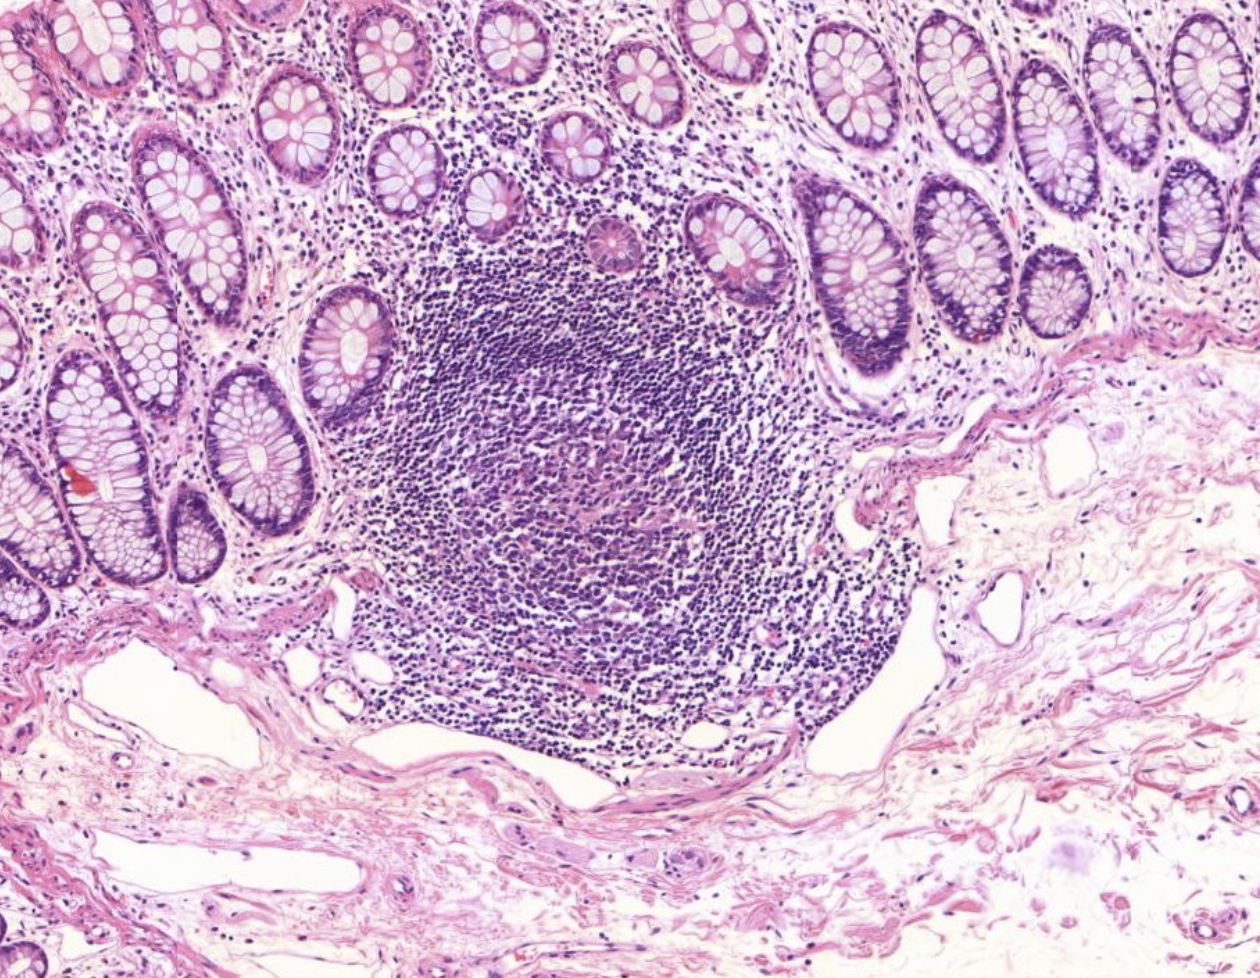

40) Was sieht man hier im Mittelpuntt?

Histopathologisches Bild: Kolonschleimhaut

Es zeigt sich Lymphatisches Gewebe der Colonschleimhaut, sogenannte Pleyer Plaques.